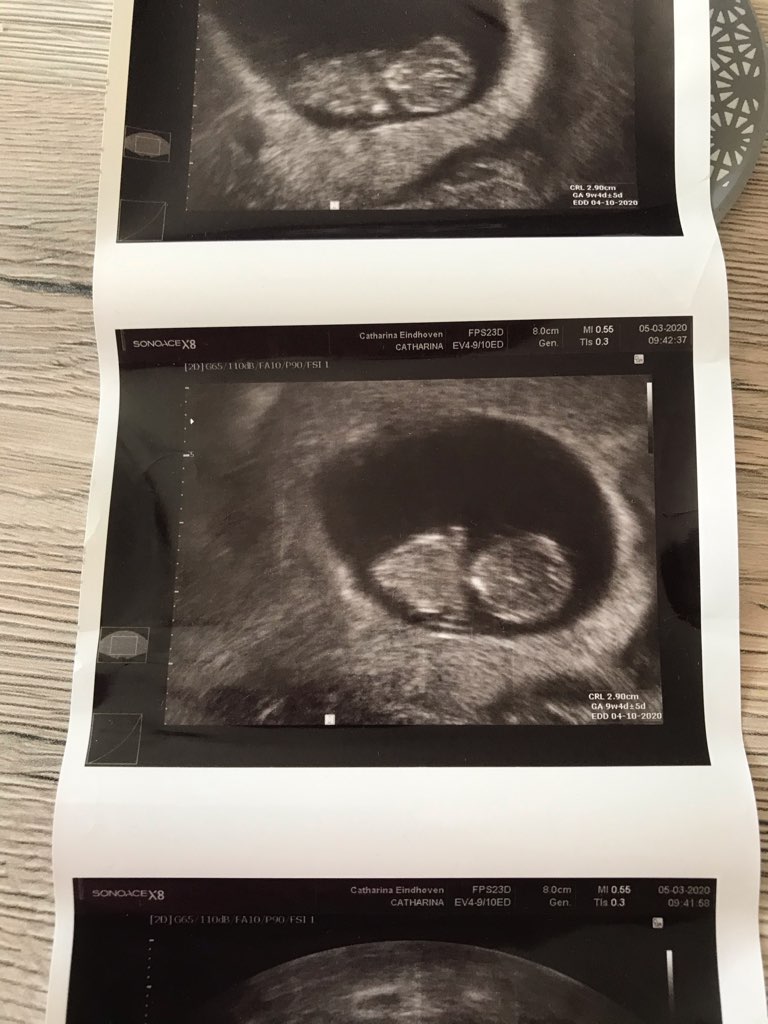

Chciałam przedstawić moje niewidzialne dziecko...podobno wina niepelnego pęcherza...

To był 9. Też tak myślę że to jego USG... Ja byłam w takim prewatnym gabinecie małym. Bałam się strasznie iść do naszego szpitala. W naszym szpitalu w Harlow zarazili już kilka osób coronavirusem... Śliczne to Twoje zdjęcie, wszystko widać.Ja zawsze mam pusty pęcherz dla mnie to wina słabej jakości usg a nie ze pęcherz pusty, który tydzień tu na usg?